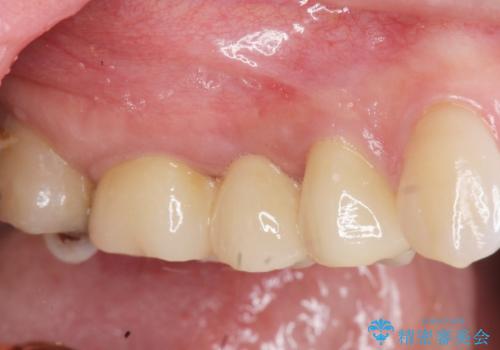

虫歯による歯の喪失 ジルコニアブリッジの製作

- 大きく歯が欠けてしまった虫歯の治療を希望され来院されました。

虫歯による歯の崩壊で歯を残すことが難しかったので抜歯を行い、インプラント・入れ歯ではなくブリッジによる咬合機能の回復を希望されました。